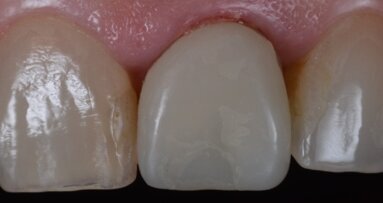

A 7 giorni è stato eseguito un controllo per verificare lo stato dei tessuti gengivali e continuare a motivare la paziente riguardo all’esclusione dai carichi masticatori (Fig. 9). A 90 giorni è stato rimosso il provvisorio per procedere al restauro ceramico. Nonostante la superficie SLActive preveda un accorciamento dei tempi di integrazione, è stato deciso un tempo di attesa convenzionale per accertarsi della stabilità dei tessuti molli perimplantari (Figg. 10-12). È stato eseguito un workflow digitale a partire dall’impronta ottica, fino alla realizzazione di un restauro in Zirconia precolorata e stratificata vestibolare (Dental Direkt 1200 e Creation ZI-CT) su base titanio (Figg. 13, 14). Il restauro è stato consegnato mediante avvitamento a controllo di torque secondo le indicazioni della casa produttrice (Figg. 15, 16).

Fig. 15_Consegna della corona ceramica avvitata.